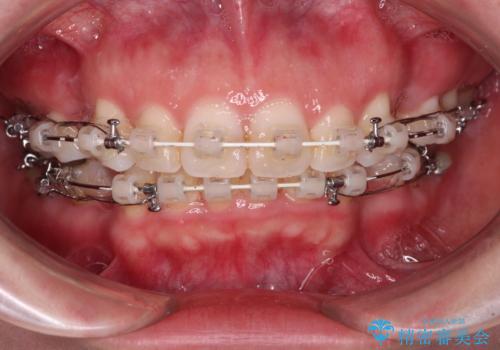

- 矯正装置

- 審美装置

- 口元の閉じにくさと、奥歯の咬み合わせを気にして来院された患者様です。

左下の大臼歯2本が顕著に舌側に傾斜しているため、まずは奥歯の咬み合わせを改善をし、その後上下左右の第1小臼歯4本を抜歯することで口元を引っ込めながら整えることとしました。

奥歯の咬み合わせ改善には1年ほどの期間と処置中の噛みにくさを強いることとなりましたが、抜歯後はスムーズに治療を完了させることができました。